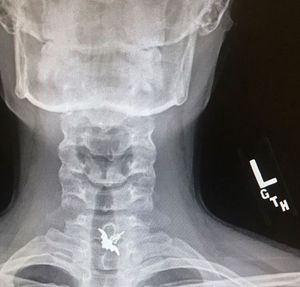

There was an old woman who swallowed a... bat earring?

Swallow

Bat

Earring